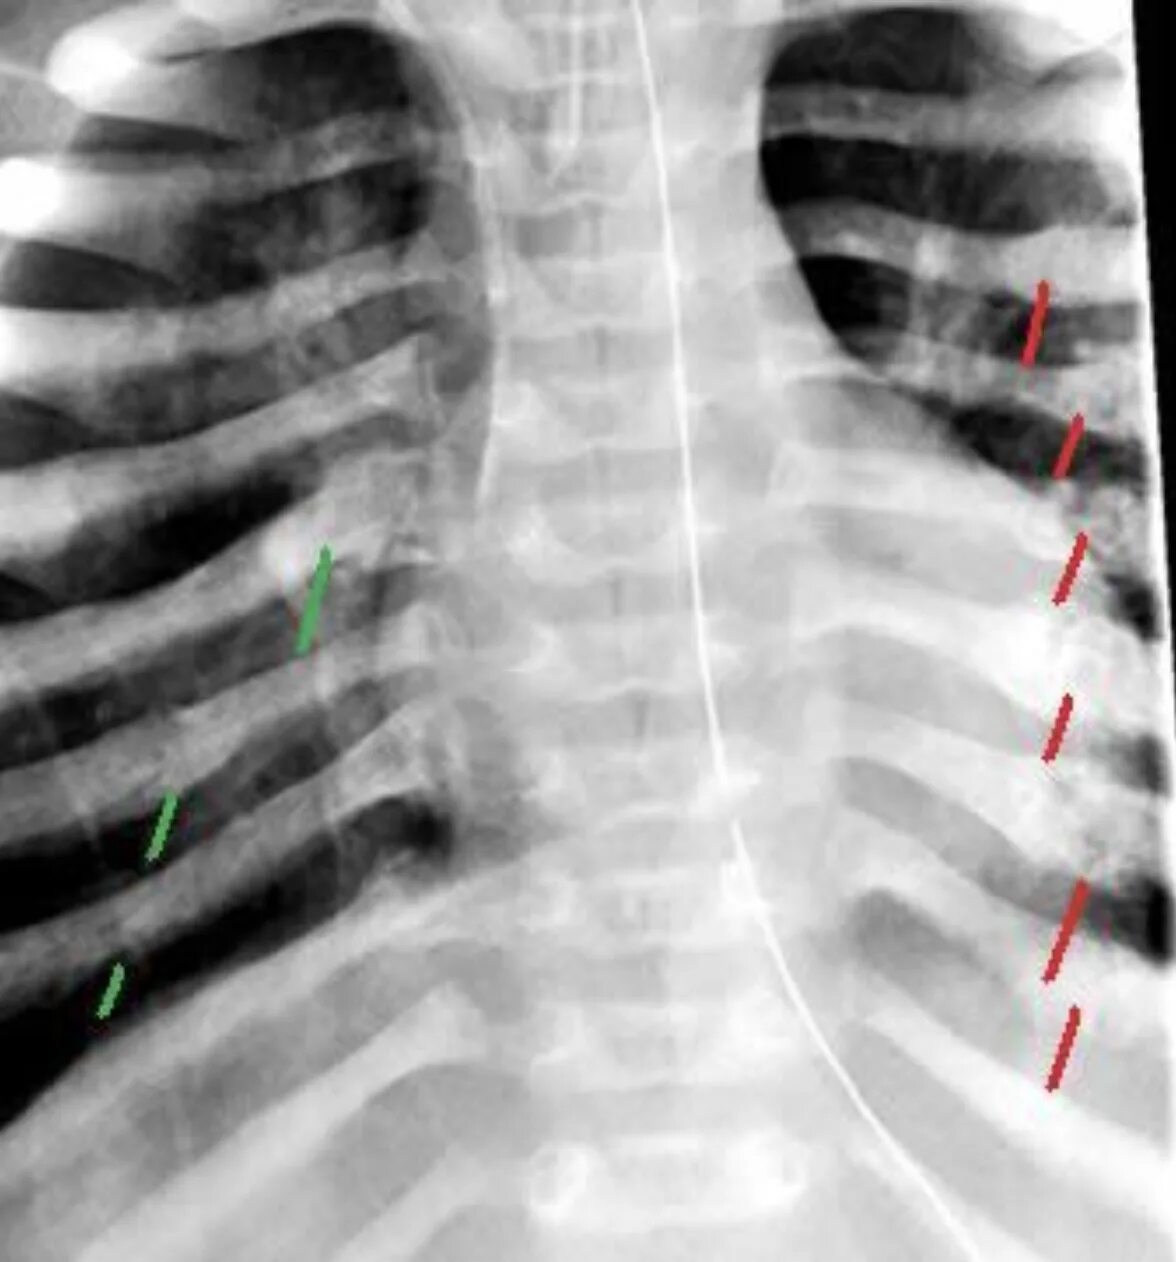

Сколько срастается ребро при переломе